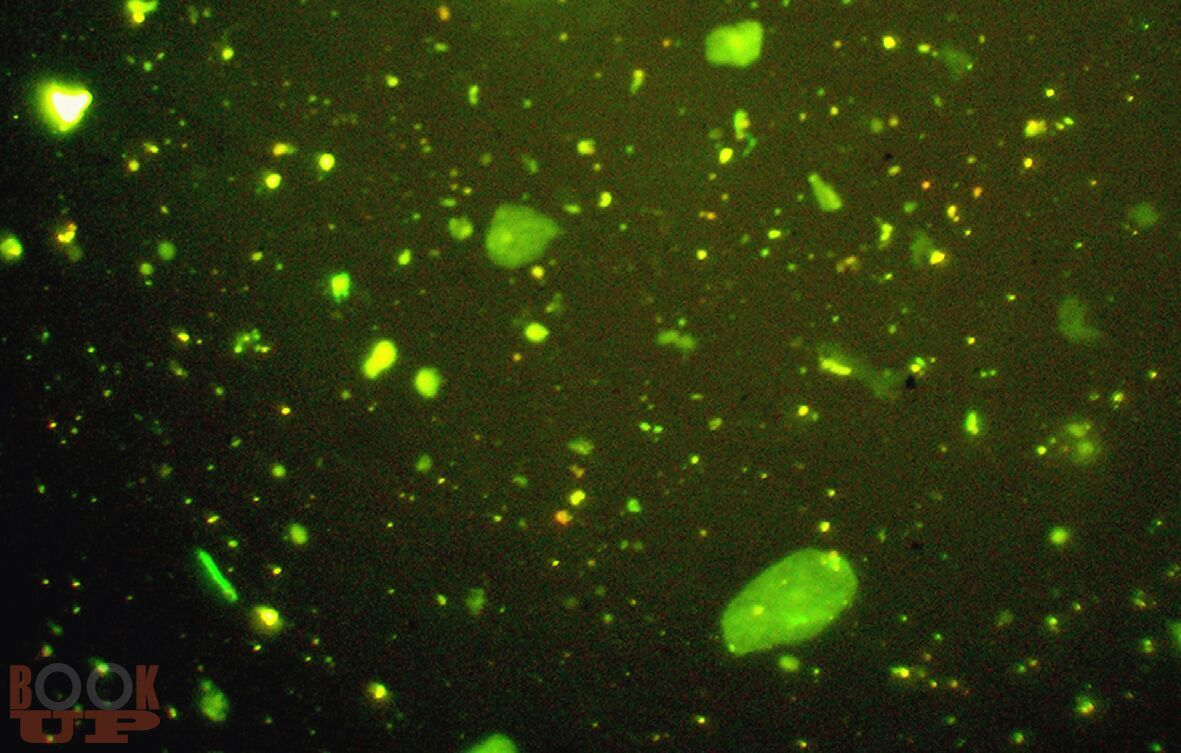

В монографии представлены новые данные об исследовании мочи и желудочного содержимого. Впервые разработаны способы диагностики половой принадлежности мочи по различиям в содержании ядросодержащих и безъядерных клеток и достоверного установления наличия желудочного содержимого на вещественных доказательствах и во внешней среде. В работе приведены результаты исследований о влиянии различных факторов на клеточный состав мочи и на выявляемость желудочного содержимого.